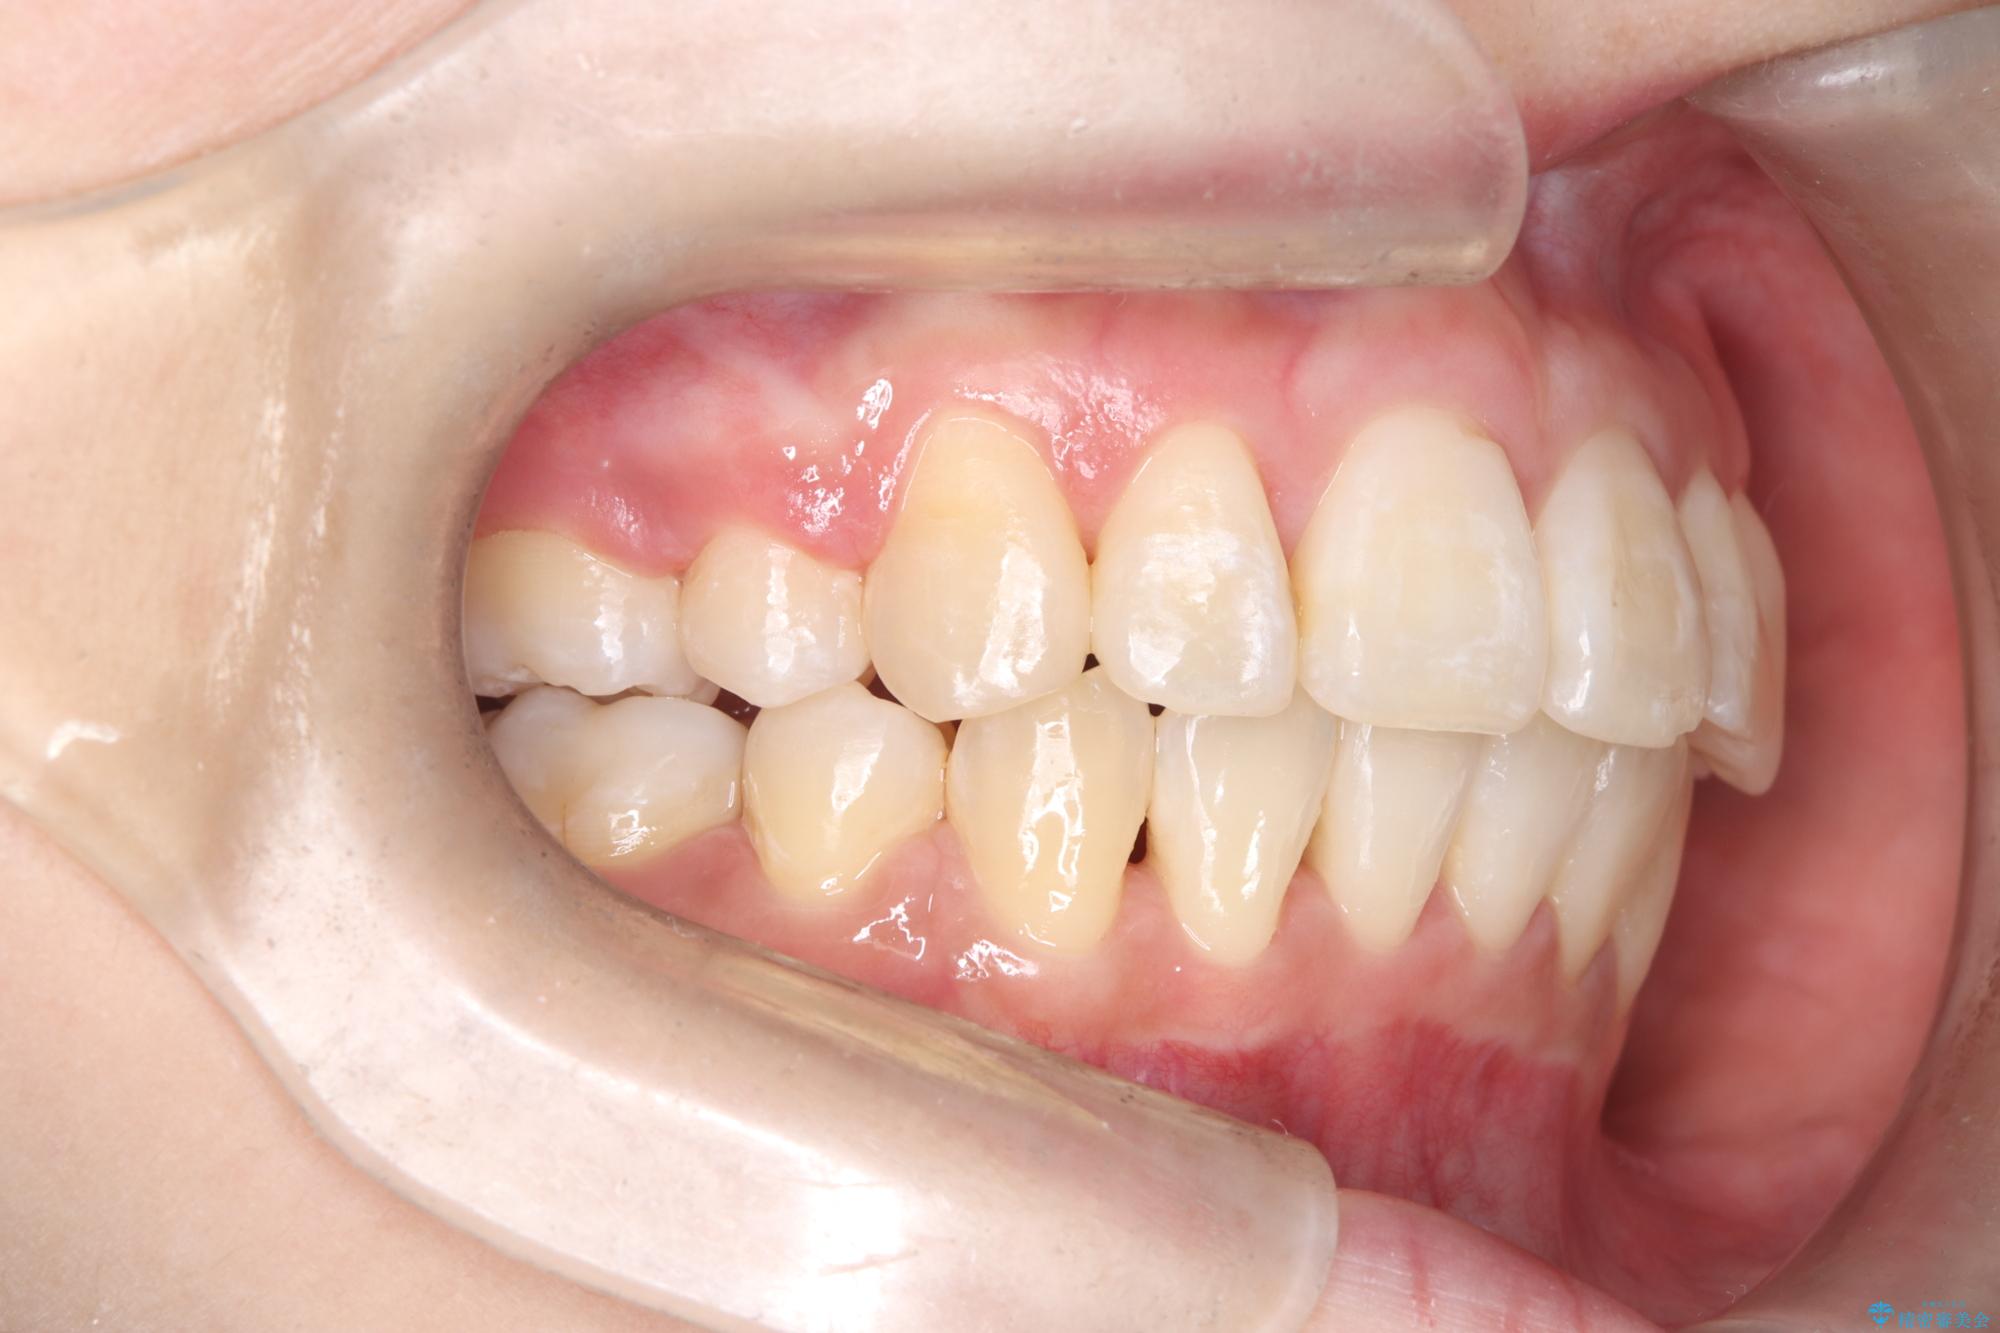

八重歯: 突出していた八重歯を歯列内に誘導し、デコボコを解消しました。

正中のズレ: 歯を左右対称に移動させることで、上下の歯の中心線を正確に合わせ、顔全体のバランスも改善しました。

治療の結果、長年気にされていた八重歯と正中のズレが解消し、機能的にも整った理想的な歯並びを獲得。目立たない装置で治療を完遂し、自信を持って笑える美しい笑顔を手に入れていただけました。